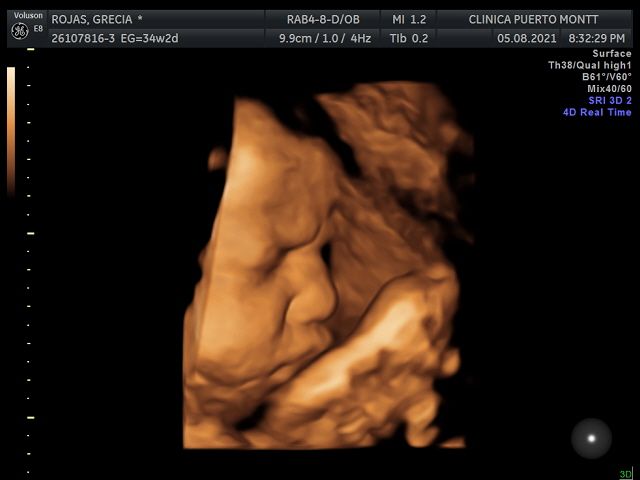

Ecografia Obstetrica y ginecologia

Ecografia Doppler obstetrica

Ecografia volumétrica (3 D y 4D)

Ecografía 4D 90000 $